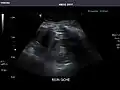

Renal ultrasonography

Ultrasound scan of a kidney (right side)

Ultrasonography of the kidneys is essential in the diagnosis and management of kidney-related diseases. The kidneys are easily examined, and most pathological changes in the kidneys are distinguishable with ultrasound.[7]